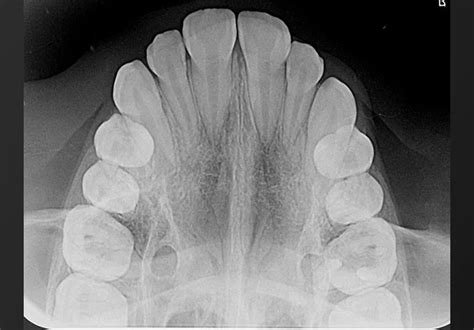

Se presenta el caso de una paciente de 48 años, que acudió por fractura del incisivo central superior derecho. La paciente era portadora de prótesis fijas en el resto de incisivos superiores. Tras introducir en el programa de planificación de cirugía de implantes (RealGuide® 3DIEMME, Cantù, Italia) los archivos DICOM de la TCHC, el STL de la arcada y del encerado virtual del diente a sustituir, se obtuvo el modelo tridimensional de la paciente.

Imagen clínica frontal y oclusal donde se observa el resto radicular.

Los sistemas de planificación permiten posicionar la plataforma del implante en la posición tridimensional ideal para asegurar una correcta emergencia protética y conseguir resultados estéticos adecuados. En este caso clínico, en la imagen axial de la TCHC se observó como la cortical vestibular era muy fina (<0,5 mm) y que en el corte coronal la morfología de la cortical era adecuada y no había defecto de los tejidos duros que implicara la necesidad de realizar una regeneración ósea.